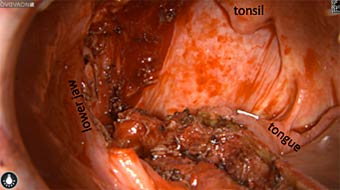

Intraoperative imaging panitumumab-IRDye800 (fluorescence)

Primary tumor prior to resection

Wound bed post re-resection of tumor

Fluorescence imaging of the tumor was performed prior to resection and after resection to “check” the wound bed. In the upper row the tumor is clearly visible with fluorescence and in the bottom row you can see that the wound bed is empty – there is no suspicious fluorescence left. The middle column of tiles show the fluorescence signal in black and white where the “white” represents the tumor and the black the background (= no fluorescence signal). The right column of tiles shows the overlay of the brightfield photo (in greyscale) and the fluorescence (red-yellow-blue heatmap). This image provides anatomical context to the surgeon – the surgeon can see where is the fluorescence located with regard to the tumor area.